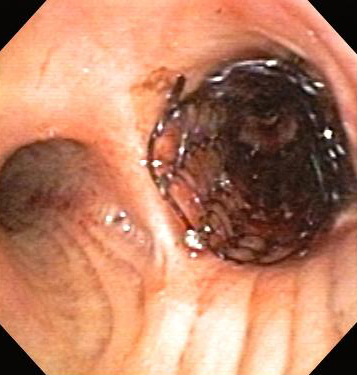

Bronchoscopic therapy for central airway obstruction of the right mainstem: post-mechanical debulking

From the collections of Jose Fernando Santacruz MD, FCCP, DAABIP and Erik Folch MD, MSc; used with permission